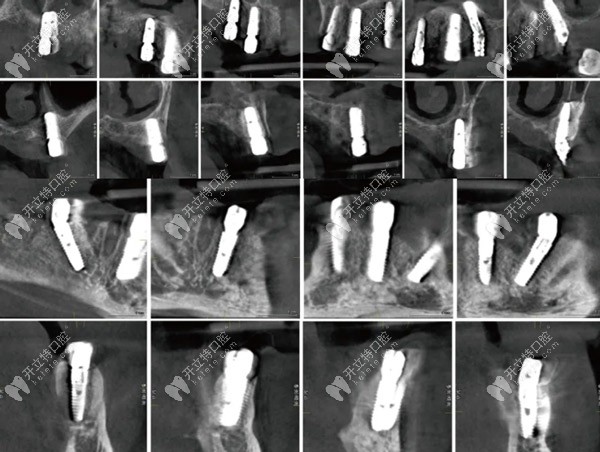

術(shù)后即刻CBCT種植體冠狀、矢狀面影像

術(shù)后即刻CBCT種植體冠狀、矢狀面影像▲

下頜導(dǎo)板固定后先鋒鉆備洞,骨修整于35,32,42,45位點(diǎn)植入Osstem Ts植體4.5-13mm(2顆)、4.0-11.5mm(2顆)所有的植體初期穩(wěn)定性均達(dá)到35Ncm以上。安裝復(fù)合基臺(tái)(30Ncm)及保護(hù)帽縫合。

拍攝CBCT檢查各植體三維位置后,取下復(fù)合基臺(tái)保護(hù)帽,安裝開(kāi)口印模帽并以GC技工樹(shù)脂做剛性連接,取硅膠印模。